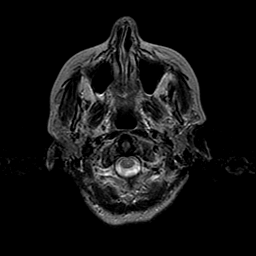

Metastatic Adenocarcinoma of the Colon: T2-weighted MR -- Slice #1

[Home][Help][Clinical] Slice 1